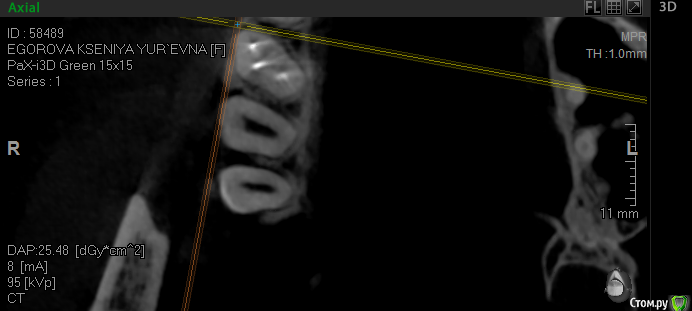

krokomot Опубликовано 17 октября, 2019 Поделиться Опубликовано 17 октября, 2019 Проблема в фуркации шёчных каналов, есть расширение щели и сниженный показатель денситометрии кости прилегающей к этому участку, в отличие от других участков, это означает что кость там находится в процессе атрофии. Ссылка на комментарий

vse32 Опубликовано 18 октября, 2019 Автор Поделиться Опубликовано 18 октября, 2019 Проблема в фуркации шёчных каналов, есть расширение щели и сниженный показатель денситометрии кости прилегающей к этому участку, в отличие от других участков, это означает что кость там находится в процессе атрофии.Самая привлекательная для меня версия. Считаете проблема в бифуркации? Ссылка на комментарий

krokomot Опубликовано 18 октября, 2019 Поделиться Опубликовано 18 октября, 2019 По кт пломбировку каналов и состояние корней судить нельзя, только опосредовано через состояние периодонтальной щели и костной ткани, это относительно достоверные признаки, при трещине или переломе мы не увидим трещину корня, но увидим измененя косиной ткани. В данной ситуации по кт сомнительную зону я обнаруживаю только в области фуркации щечных каналов, и то я вления не выраженные, хотя длительный процесс более месяца обязан был дать четкую картину на кт, но ее нет. Была у меня такая пациентка с периодонтитом переднего зуба, болел полгода, никаких рентегологических признаков указывающих на периодонтит небыло, вскрытие показало канал пустой. Ссылка на комментарий

___49___ Опубликовано 18 октября, 2019 Поделиться Опубликовано 18 октября, 2019 устье плохо визуализируется , больше ориентируюсь на анатомию корня , два скрина с отметкой и без . Ссылка на комментарий

___49___ Опубликовано 18 октября, 2019 Поделиться Опубликовано 18 октября, 2019 еще 2 скрина также с меткой и без , где четко виден канал мб2 Ссылка на комментарий